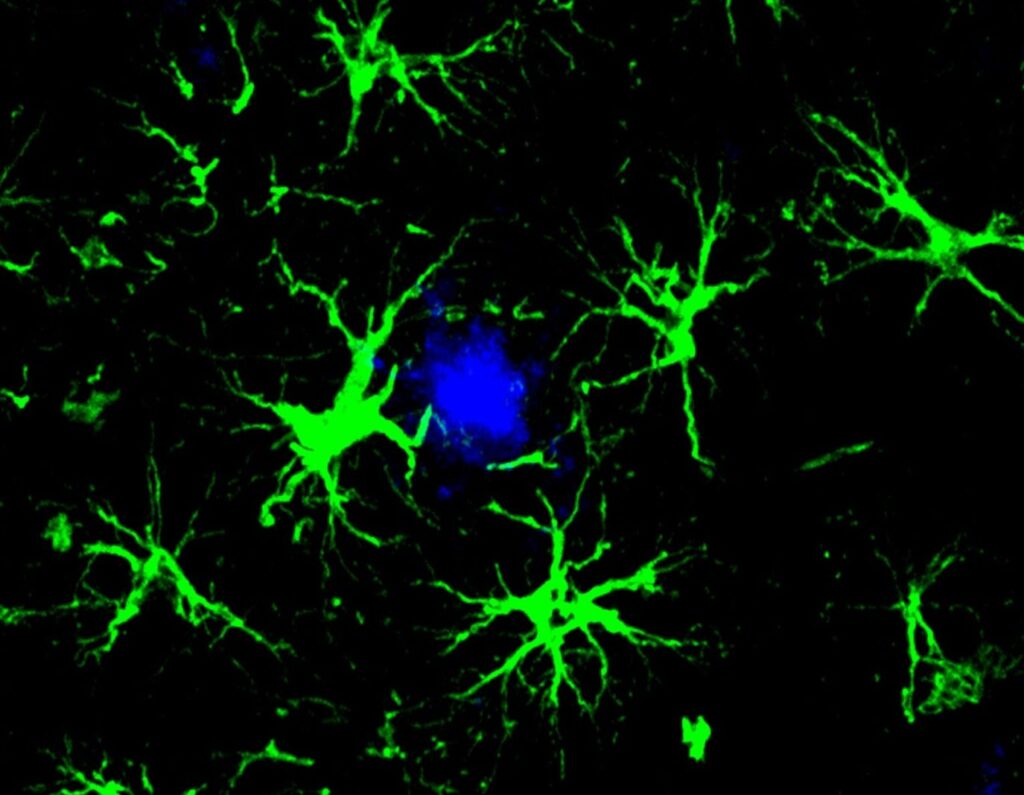

Γενετικά τροποποιημένα εγκεφαλικά κύτταρα «τρώνε» τις πλάκες του Αλτσχάιμερ

Ερευνητές στο Washington University μετέτρεψαν αστροκύτταρα — κύτταρα-υποστήριξης του εγκεφάλου — σε μηχανές καταστροφής της τοξικής αμυλοειδούς πρωτεΐνης που συνδέεται με τον Αλτσχάιμερ. Μία μόνο ένεση σε ποντίκια αρκούσε για να μειώσει…